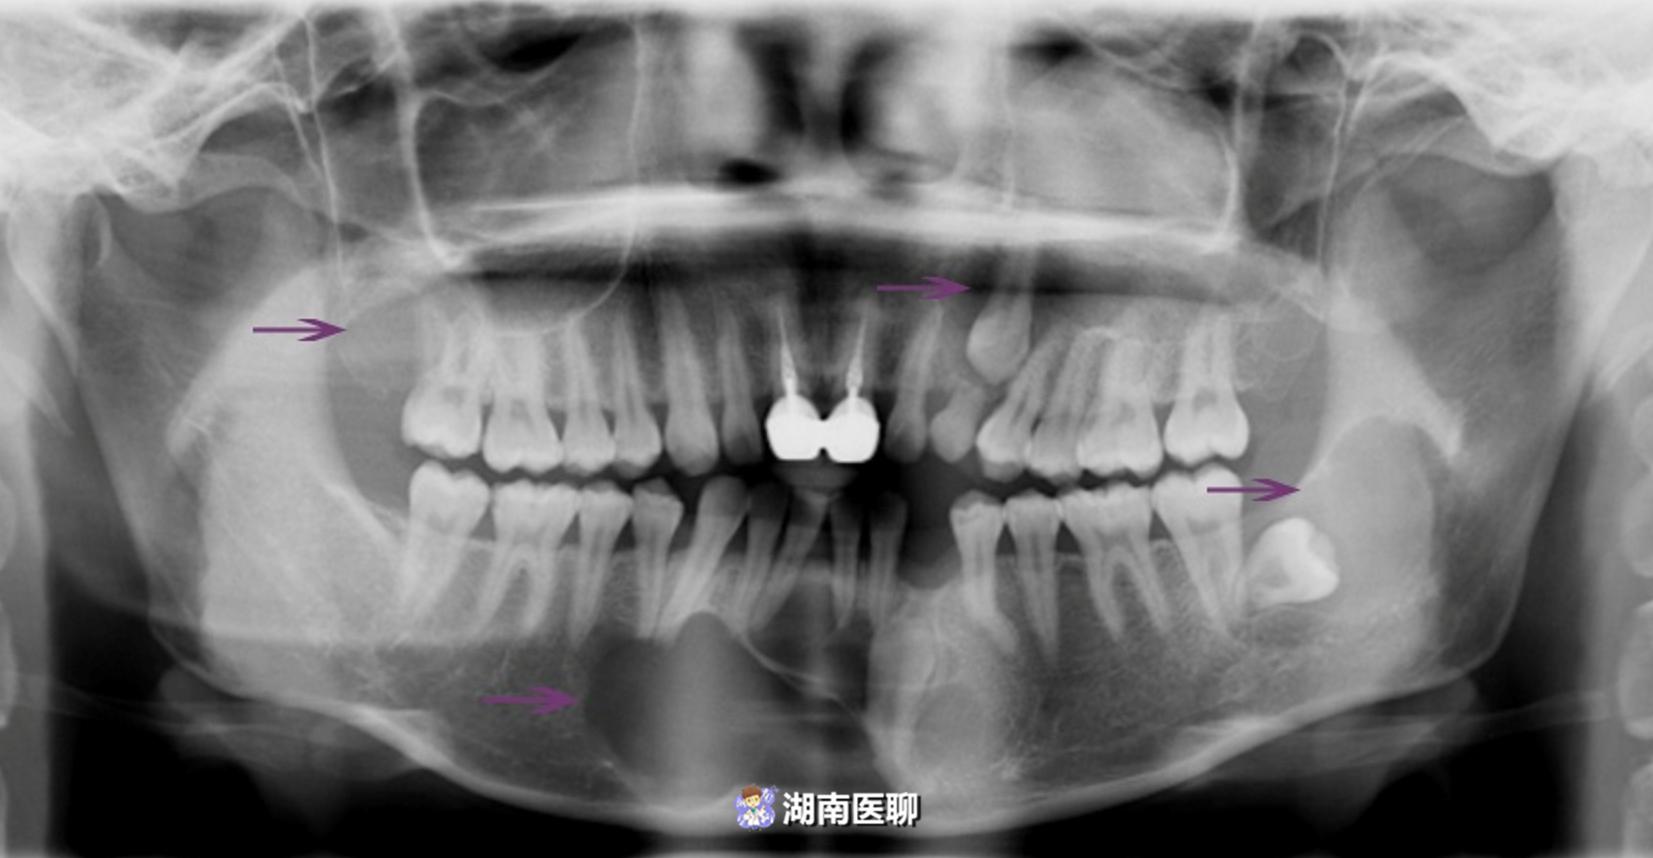

(一女性患者:四处颌骨囊肿,上颌骨囊肿均已突破上颌窦,囊肿内多含未萌出牙齿)

蒋校文博士对她进行了详细的检查,确定囊肿数量及位置。

其中,口腔损害主要表现为复发性颌骨囊肿,约见于90%的患者。

此类囊肿好发于下颌骨,可同时累及上下颌骨。

包括进行口腔全景片或CBCT检查,排除颌骨内囊肿形成,及早发现,及早处理。